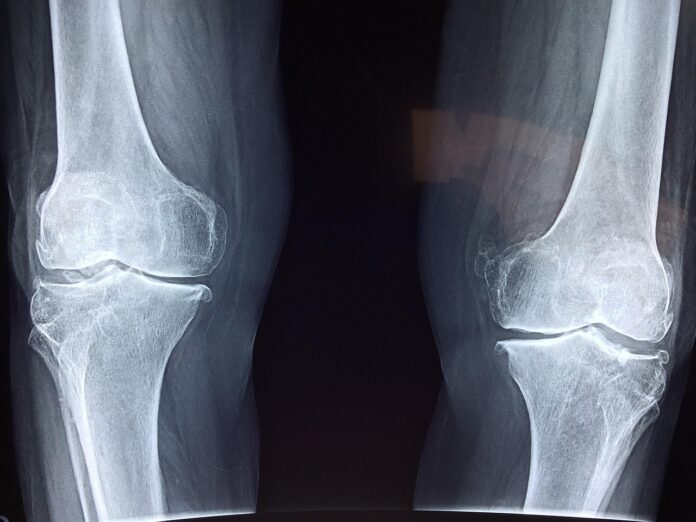

Laboratorijski testi so potrdili, da je “Bone 02” uspešno prestal merila za varnost in učinkovitost. V enem izmed poskusov je bil postopek zaključen v manj kot 180 sekundah ali treh minutah, medtem ko bi konvencionalne metode zdravljenja zahtevale večji rez za vstavitev jeklenih plošč in vijakov. Lepilo je bilo uspešno preizkušeno na več kot 150 pacientih. Zlepljene kosti so pokazale največjo vezno moč več kot 400 funtov, strižno trdnost približno 0,5 MPa in tlačno trdnost okoli 10 MPa, kar poudarja, da ima izdelek potencial za zamenjavo tradicionalnih kovinskih vsadkov. Znanstveniki so navedli, da bi lahko tudi zmanjšalo tveganja za reakcije in okužbe.